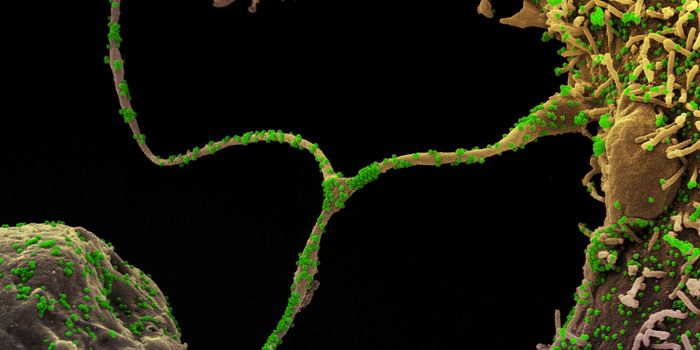

APR 04, 2022Cell & Molecular BiologyAbout 1.5 million new HIV infections are thought to have occurred last year, and while COVID-19 has dominated concerns a ...

FEB 21, 2022Cell & Molecular BiologyTwo people have been cured of HIV, and now, a US woman joins them. In this third case, stem cell transplants were being ...

NOV 30, 2021ImmunologyHIV is a master of disguise. Once the virus enters the body, it has a number of sophisticated mechanisms through which i ...

NOV 22, 2021MicrobiologyThough treatments are available, there is no cure or vaccine from HIV, which impacts about 38 million people worldwide. ...

SEP 06, 2021MicrobiologyHIV vaccines have remained elusive in part because the virus has a powerful ability to mutate, and there are so many str ...

JUN 24, 2021ImmunologyA new study has revealed how stem cells can be used to amplify immune responses to HIV, the virus that causes AIDS. The ...